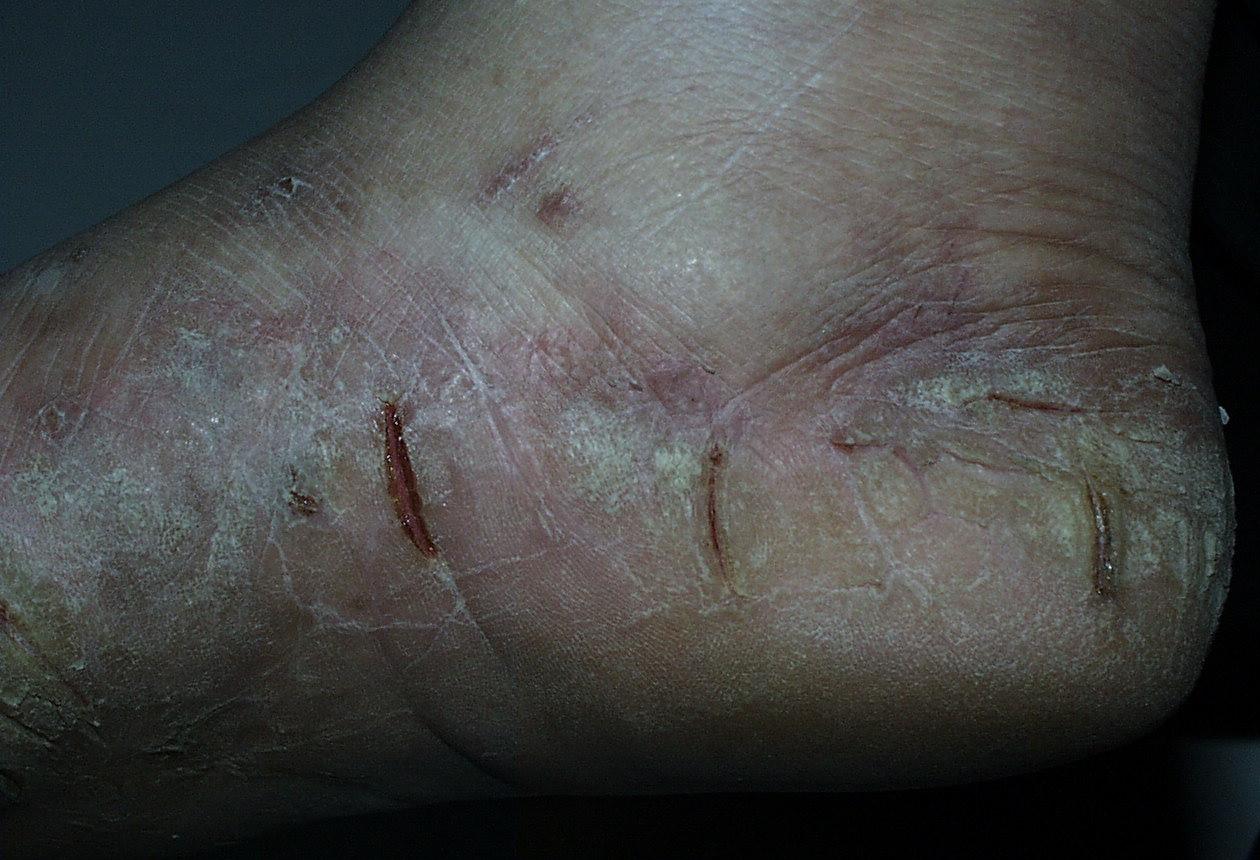

Acute Ulcerative Type.

Rampant bacterial co-infection, most often from Gram negatives in combination with T. mentagrophytes, produces vesiculopustules and large areas of purulent ulceration on the plantar surface. Cellulitis, lymphangiitis, lymphadenopathy, and fever are frequently associated.

The vesiculo-bullous and acute ulcerative types commonly produce a vesicular id reaction, either as a dyshidroticlike distribution on the hands or on the lateral foot or toes.